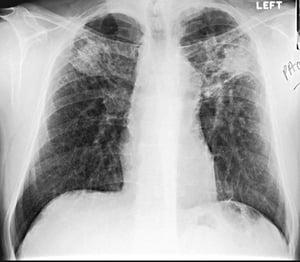

Silicosis—Simple

Image courtesy of David W. Cugell, MD.

Chronic silicosis is categorized on chest imaging as simple or complicated. In patients with simple silicosis, there is upper lobe predominance of bilateral 1- to 3-mm reticulonodular opacities. Calcified hilar and mediastinal lymph nodes are common and occasionally resemble eggshells; however, eggshell calcification is not pathognomonic for silicosis. Pleural thickening is uncommon unless a severe parenchymal disease abuts the pleura.